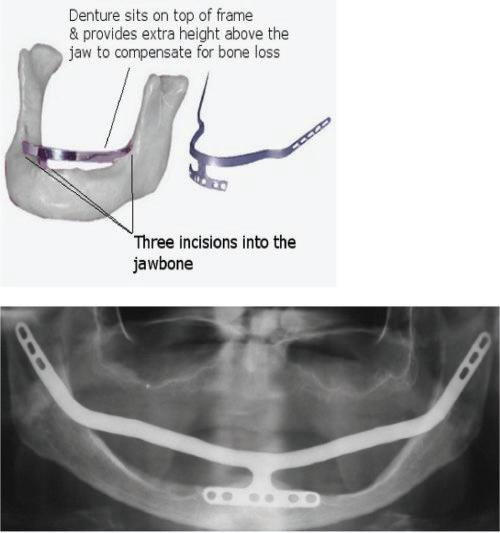

During 1939–60s the concept of the ‘in the bone’ (endosteal) implant arose with the first cylindrical endo-osseous solid screw implant with threads both internally and externally with a smooth gingival collar and healing cap being placed. Following this during the 1940s, a spiral stainless steel post type endosseous implant with a design that allowed bone to grow into the implant emerged and Dahl in Germany, around the same time, introduced the concept of the subperiosteal implant with mucosal inserts (Figure 1.1). This implant was made of cobalt-chromium molybedenum with a direct impression of the struts on the ridge crest taken to construct the denture. Throughout the 1940s–50s variations on the original Dahl design emerged in an attempt to make the provision of implants simpler and included the use of vitallium implants in 1948, the Linkow endoosseous blade vent implant in 1966 with different designs for the maxilla and mandible (Figure 1.2), the ramus frame implant in 1970, made of stainless steel (Figure 1.3) and mandibular transossteal implant which engaged the lower border of the mandible with inserts projecting into the mouth to support a prosthesis (Figure 1.4). The ramus frame and tranossteal implants were predominantly designed for patients with atrophic mandibles who had difficulties wearing dentures and were used to aide denture retention to improve function.

Figure 1.1 Subperiosteal implants in the mouth.

Figure 1.3 Ramus implants.